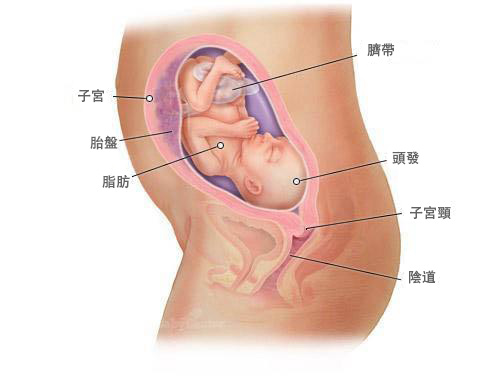

懷孕25周的胎兒是什麼樣子 附 胎兒每周發育標準參考表 壹讀

懷孕25周胎寶寶是怎麼樣的呢 孕婦要注意什麼呢 看完很喜人 壹讀

懷孕期第25週 寶寶階段發展 Superbaby

懷孕第25週 Mamaway媽媽餵懷孕哺乳育兒百科

懷孕25周的胎兒是什麼樣子 附 胎兒每周發育標準參考表 壹讀

懷孕25周胎寶寶是怎麼樣的呢 孕婦要注意什麼呢 看完很喜人 壹讀

懷孕25周的胎兒是什麼樣子 附 胎兒每周發育標準參考表 每日頭條